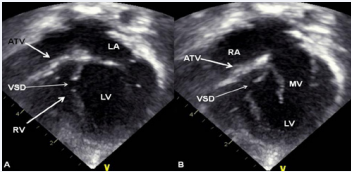

Figure 5 Selected video frames from apical four-chamber, 2-dimensional echocardiographic views of a neonate with tricuspid atresia showing an enlarged left ventricle (LV), a small right ventricle (RV), and a dense band of echoes at the site where the tricuspid valve echo should be (ATV; thick arrow) with closed (A) and open (B) mitral valve (MV). A moderate sized ventricular septal defect (VSD; thin arrow) is shown. LA, Left atrium; RA, Right atrium [36].™Figure 1

Figure 5: Selected video frames from apical four-chamber, 2-dimensional echocardiographic views of a neonate with tricuspid atresia showing an enlarged left ventricle (LV), a small right ventricle (RV), and a dense band of echoes at the site where the tricuspid valve echo should be (ATV; thick arrow) with closed (A) and open (B) mitral valve (MV). A moderate sized ventricular septal defect (VSD; thin arrow) is shown. LA, Left atrium; RA, Right atrium [36].™Figure 1

M-mode echocardiograms, while not diagnostic, are useful in evaluating the size of the left atrium and left ventricle and left ventricular systolic function. An enlarged RA, left atrium, and left ventricle and a small RV are seen by 2D echocardiography (Figure 5). In the most common muscular type, the atretic tricuspid valve is imaged directly as a dense band of echoes at the site where the tricuspid valve should be (Figure 5). Apical four-chamber and subcostal views are best to demonstrate the anatomy. The morphology of the atretic tricuspid valve as reviewed above and in Figure 1, namely muscular, membranous, valvular, Ebstein’s, AV canal, and unguarded valve with muscular shelf, may be distinguishable from each other on careful inspection of the site of the tricuspid valve.

Echo-Doppler studies are also useful in demonstrating an ASD/PFO with a right-to-left shunt (Figure 6) and a VSD with a left-to-right shunt (Figure 7).